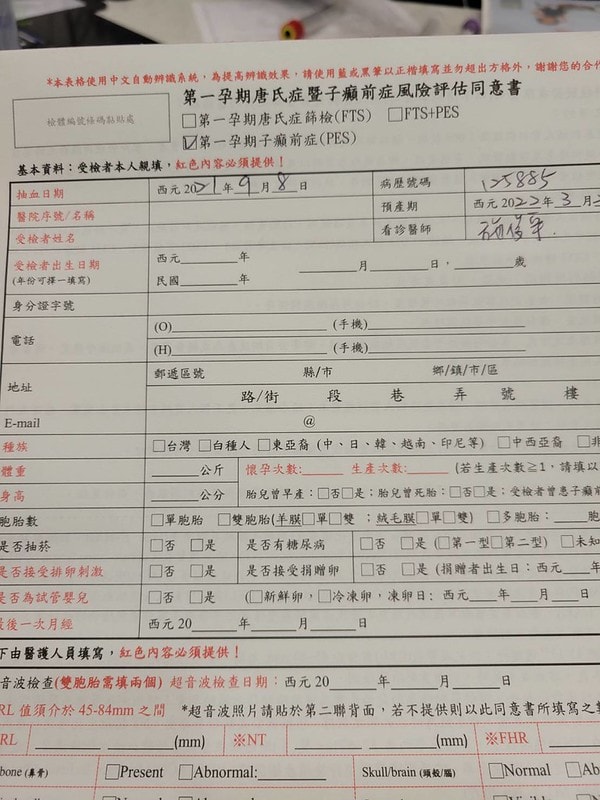

我做了NIPT+五合一+子癲前症總共大概三樣檢查

花了三萬二左右

子癲前症也是高齡產婦可以做的檢查之一,發生率約5%

但如果發生對於孕婦來說很嚴重唷~

根據衛生署統計,過去5年台灣地區造成孕產婦死亡的三大原因是:

羊水栓塞、子癲前症(妊娠毒血症)以及產後大出血;

每年全球約有5萬名孕婦

因為罹患子癲前症(妊娠毒血症)及其相關合併症而不幸死亡。

根據估計,亦約有15%的早產兒

是因為為了控制母親之子癲前症(妊娠毒血症)病情而不得不被提早分娩出來

所以我就是做了以上說的NIPT+五合一+子癲前症這三樣檢查